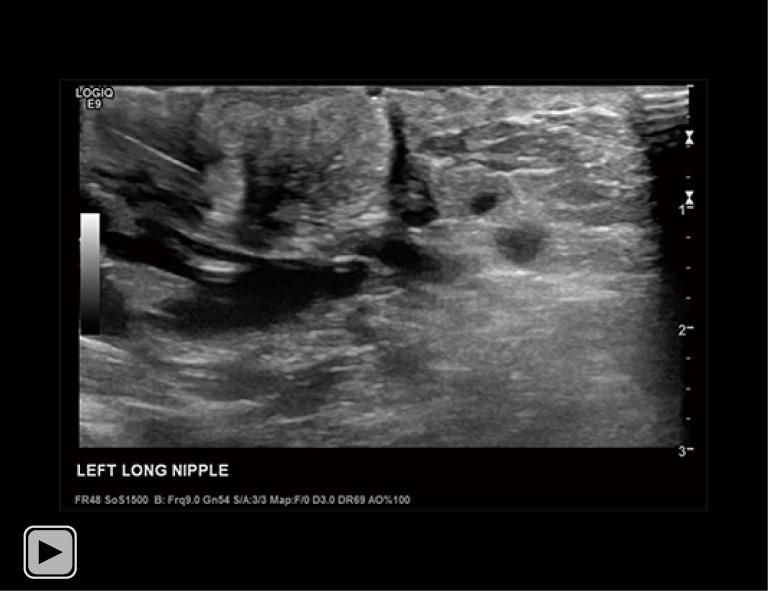

CASE DESCRIPTION

A 34-year-old lactating female presented with a 3-month history of worsening left breast and nipple pain radiating to the left upper outer quadrant, not relieved with conservative therapies. The physical exam revealed a small indentation and a small palpable nodule of the left nipple. There was no associated erythema or redness. Targeted ultrasound and subareolar magnification views revealed findings most consistent with a probably benign inspissated clogged milk duct. Given the patient's history, inability to express milk from the left breast, and plan to lactate for another year, ultrasound-guided aspiration was desired. Post-aspiration images demonstrated complete resolution of the nipple mass. Pathology revealed blood and proteinaceous material, in keeping with the diagnosis of inspissated clogged milk duct. Following the procedure, the patient's symptoms resolved completely.

一名34岁的哺乳期女性,左乳房和乳头疼痛加剧3个月,疼痛放射至左乳房外上象限,保守治疗未能缓解。体格检查发现左乳头有一个小凹陷和一个可触及的小结节。无相关红斑或发红。针对性超声检查和乳晕下放大视图显示的结果最符合可能为良性的浓缩性乳腺管堵塞。鉴于患者的病史、左乳房无法挤出乳汁以及计划再哺乳一年,希望进行超声引导下抽吸。抽吸后的图像显示乳头肿块完全消失。病理检查显示为血液和蛋白质物质,符合浓缩性乳腺管堵塞的诊断。手术后,患者症状完全缓解。